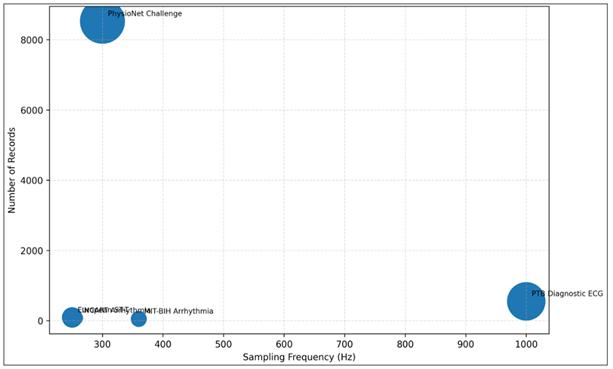

The ECG analysis systems are also evaluated based on the variety and quality of the datasets on which the model is trained and evaluated. The variability of the different datasets can be in terms of signal sampling frequency, number of recorded patients and duration of recorded signals. These properties determine the extent of generalization of trained models to clinical settings in the real world. The distribution of the dataset used in the study is shown in Figure 4 which is a bubble chart that explains the correlation between the sampling frequency and the quantity of the records in the popular ECG datasets. The bigger bubbles denote bigger datasets including more patient recordings, which mean that machine learning algorithms have more training data. The graphical representation demonstrates that big data like the PhysioNet challenge dataset offer a large amount of data on which to train powerful classification models.

Figure 6 Dataset Landscape for ECG Signal Analysis